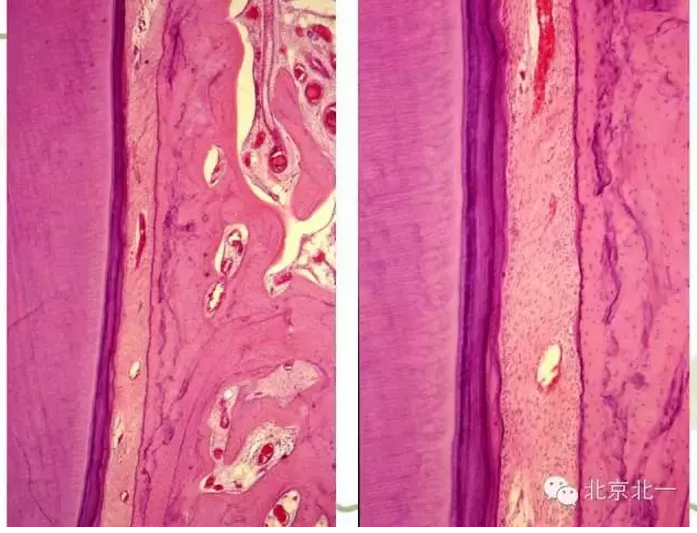

【牙周學(xué)習(xí)】牙周組織--基礎(chǔ)知識篇(下)